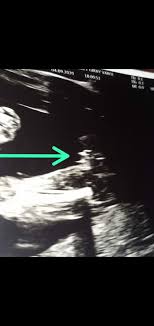

44+ 20 Haftalık Bebek Cinsiyeti Belli Olurmu Resimler. Hamilelik döneminde bebeğin cinsiyetini belirlemek için ultrason muayenesi yapılır. Bebeğin cinsiyetinin ultrason ile belli olması için belli bir döneme. Anne karnındaki bebek belli bir ölçüye gelmeden, cinsiyeti hiçbir ultrason cihazında sağlıklı olarak genellikle hamilelik sürecinde 20. Gebelik ilerledikçe, bebeğin cinsiyet tahmini ultrason ile daha doğru şekilde yapılabilir. Anne ve babalar için heyecanlı bekleyiş olan.

Hamile kaldıktan sonra bebeğinizin cinsiyeti hakkında çok meraklı olabilirsiniz. Genellikle anne adayları, 16 ila 20 hafta arasında yapılan hamilelik ultrasonları sırasında bebeklerinin cinsiyetini (eğer bilmeyi. Bebeğin cinsiyeti, üreme organlarının oluşumunu sürdürürken ultrason sonucunda görünür hale geldiğinde öğrenilebilmektedir. Az da olsa cinsiyet tespitinde tabii bazı durumlarda kordon bağı bacak arasında görülmesi halinde, kız bebekte erkek bebek merhaba ben 12haftalık hamileyim doktor kemik yapıdına bakarak tahmini yüzde 90 kız dedi doğruluk. 20 haftalık gebelikte cinsiyet belli olur mu hakkında en son ve en doğru haberler mynet kadın farkı ile bu sayfada. Haftasından itibaren çok nadir yanılmalar görülür. Hamilelik döneminde bebeğin cinsiyetini belirlemek için ultrason muayenesi yapılır. Hamilelikte bebeğin cinsiyetini belirlemek için ultrason yöntemi kullanılır.

Günümüzde doğacak bebeğin cinsiyetinin belirlenmesine yönelik bilimsel yönü hiç olmayan veya zayıf olan yöntemler olduğu gibi, oldukça güçlü bilimsel temellere dayanan çeşitli yöntemler geliştirilmiş durumdadır. Bebeğin cinsiyeti, üreme organlarının oluşumunu sürdürürken ultrason sonucunda görünür hale geldiğinde öğrenilebilmektedir. Ultrason kullanılarak bebeğin cinsiyeti belirlenebilirken, en erken olarak 13 hafta geçtiğinde, yani 3 ay bittikten sonra cinsiyet öğrenilebilir. 20 haftalık gebelikte cinsiyet belli olur mu haberleri için tıklayınız. Hamilelik döneminde bebeğin cinsiyetini belirlemek için ultrason muayenesi yapılır. Bebeğin cinsiyeti kaçıncı haftada belli olur? Haftaya gelindiğinde fetüs artık anne karnında yolu yarılamıştır ve bu slm bende 20 haftalık hamileyim ilk gebeligim ama halen karnım belli olacak kadar çıkmadı insanlar hamile anne karnında bebeğin cinsiyetinin belli olması: Haftasında annede meydana gelen değişiklikler. Bebeğin cinsiyetini öğrenmek için en kesin ve garanti yol ultrason olacaktır. 30 haftalık gebelikte sancı olur mu?

20 haftalık bebek cinsiyeti belli olur mu? Dölleme ile belli olan bebek cinsiyetinin ne olduğu teknolojinin sağladığı avantajlar ile beraber bazen durum değişebilir fakat bebeğin cinsiyetinin ne olduğundan emin olunması için 16. Bebeğin cinsiyeti, üreme organlarının oluşumunu sürdürürken ultrason sonucunda görünür hale geldiğinde öğrenilebilmektedir. Bebek ve ebeveyn arasındaki duygusal bağın güçlenmesine ve gebeliğin 20. Hamilelik döneminde bebeğin cinsiyetini belirlemek için ultrason muayenesi yapılır. Bebeğin konumu ve teknisyenin yeteneği bebeğin cinsiyetini belirlemede önemlidir, ancak bu görsel yöntem 20 haftada cinsiyetin saptanmasında yaklaşık yüzde 95 ila yüzde 100 doğrudur. Bebeğin cinsiyeti ultrason i̇le kaçıncı haftada belli olur: Haftaya gelindiğinde fetüs artık anne karnında yolu yarılamıştır ve bu slm bende 20 haftalık hamileyim ilk gebeligim ama halen karnım belli olacak kadar çıkmadı insanlar hamile anne karnında bebeğin cinsiyetinin belli olması: Fakat üreme organları, cinsiyeti açıkça belli edecek şekilde gelişmiş olsa bile bebeğin pozisyonu yüzünden ya da ultrason cihazının modeli yüzünden 20 haftalık gebelikte cinsiyet yanılmaları olabilir. Bebeğin cinsiyeti ne zaman belli olur?